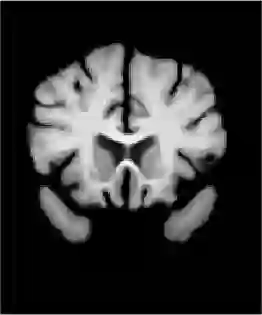

Unsupervised image registration commonly adopts U-Net style networks to predict dense displacement fields in the full-resolution spatial domain. For high-resolution volumetric image data, this process is however resource-intensive and time-consuming. To tackle this problem, we propose the Fourier-Net, replacing the expansive path in a U-Net style network with a parameter-free model-driven decoder. Specifically, instead of our Fourier-Net learning to output a full-resolution displacement field in the spatial domain, we learn its low-dimensional representation in a band-limited Fourier domain. This representation is then decoded by our devised model-driven decoder (consisting of a zero padding layer and an inverse discrete Fourier transform layer) to the dense, full-resolution displacement field in the spatial domain. These changes allow our unsupervised Fourier-Net to contain fewer parameters and computational operations, resulting in faster inference speeds. Fourier-Net is then evaluated on two public 3D brain datasets against various state-of-the-art approaches. For example, when compared to a recent transformer-based method, named TransMorph, our Fourier-Net, which only uses 2.2\% of its parameters and 6.66\% of the multiply-add operations, achieves a 0.5\% higher Dice score and an 11.48 times faster inference speed. Code is available at \url{https://github.com/xi-jia/Fourier-Net}.